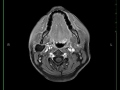

Benign Lymphoepithelial Lesion (Parotid Cyst)

22-year-old female presented for recurrent right-sided facial swelling and pain. There is a well circumscribed, T1-hypointense, T2-hyperintense, non-diffusion restricting cystic lesion involving the superficial and deep lobes of the right parotid gland. The lesion has a thin, barely perceptible wall. No suspicious enhancement. It effaces the retromandibular vein on the right. The findings are compatible with a benign lymphoepithelial lesion (BLL). BLL can be seen in the setting of HIV. Lesions may be bilateral in up to 20%, and are thought to be secondary to duct dilatation from obstruction due to lymphoid hypertrophy. Differential diagnosis includes Warthin’s tumor, first branchial cleft cyst, sialocele and cystic intraparotid nodal enlargement.